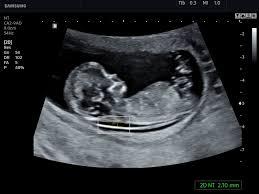

УЗИ во время беременности

УЗИ на 11-13 неделе: • Является ли нормальным раннее развитие ребенка? • Сколько там детей? • Если это беременность близнецами, то какая? • Заметны ли какие-то аномалии? • Есть ли дополнительная жидкость в области шеи (измерение толщины воротникового пространства)? Необходима ли оценка длины цервикального канала или шейки матки для определения риска преждевременных родов? УЗ исследование может определить наличие или отсутствие носовых костей для прогнозирования детей с хромосомными аномалиями. • Когда должен быть ожидаемый срок родов (исследование для определения даты родов)? Во время этого исследования есть возможность провести оценку риска хромосомных аномалий (таких как синдром Дауна).

УЗИ в 20 недель (во втором триместре/оценка анатомии плода): • Когда ожидаемая дата родов (менее достоверно, чем УЗИ на ранних сроках)? • Сколько там детей? • Развивается ли нормально ребенок ? • Существует ли подозрение на наличие каких-либо проблем у ребенка (оценка анатомии плода)? • Где находится плацента в матке? • Достаточно ли количество околоплодной жидкости?

Оценка роста плода в третьем триместре (последние 3 месяца беременности): • Нормально ли развивается ребенок? • Достаточно ли количество околоплодной жидкости? • Какое расположение ребенка? • Существует ли подозрение на проблемы, которые не могли быть выявлены раньше.